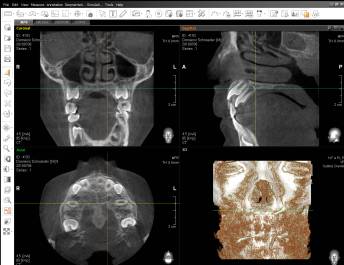

3D Röntgendiagnostik (Praxiseigenes DVT)

Die Digitale Volumentomographie (DVT) ist ein modernes, strahlungsarmes, dreidimensionales Röntgenverfahren speziell für den Zahn-, Mund- und Kieferbereich. Die präzise räumliche Darstellung der topografischen Verhältnisse, ermöglicht eine genaue Einschätzung komplizierter Situationen und Behandlungsbedingungen. Die aus einer dreidimensionalen Aufnahme gewonnenen Informationen sind hilfreich u.a. bei der Planung von Implantaten, vor Entfernung von Weisheitszähnen oder stark verlagerten Zähnen.